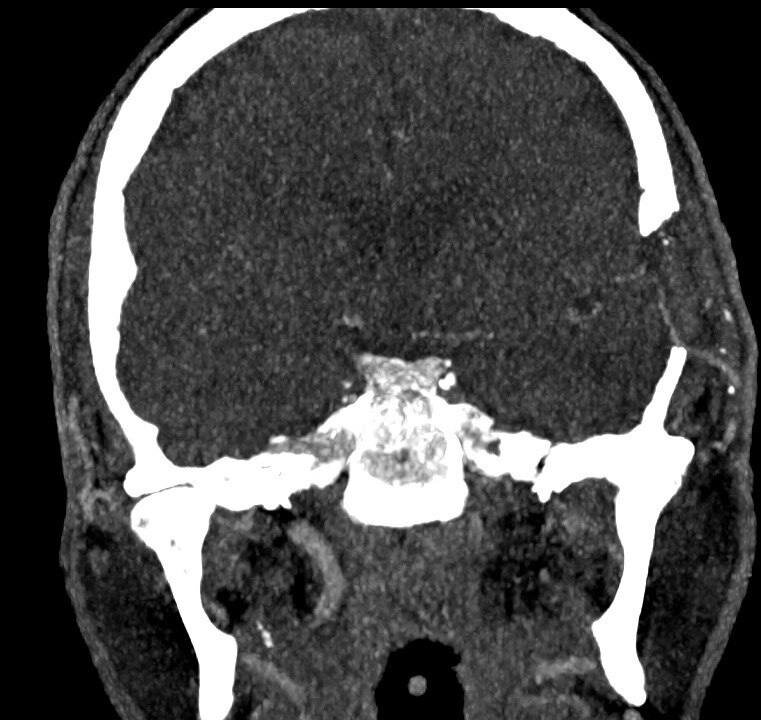

Нейрохирурги выполнили уникальную операцию 59-летнему пациенту, создав обходной путь для артерии, питающей мозг. Об этом сообщили в Минздраве Московской области.

«В течение почти четырех часов хирурги под микроскопом сшивали сосуды диаметром менее 2 миллиметров. Тем самым, мы успешно создали для кровотока новый путь», – рассказал нейрохирург Истринской больницы Николай Карпов.

На данный момент мужчину уже выписали, он находится дома на амбулаторном лечении. Контрольное обследование через месяц подтвердило: созданный «обходной путь» работает идеально, состояние пациента улучшается, а угроза повторного инсульта устранена